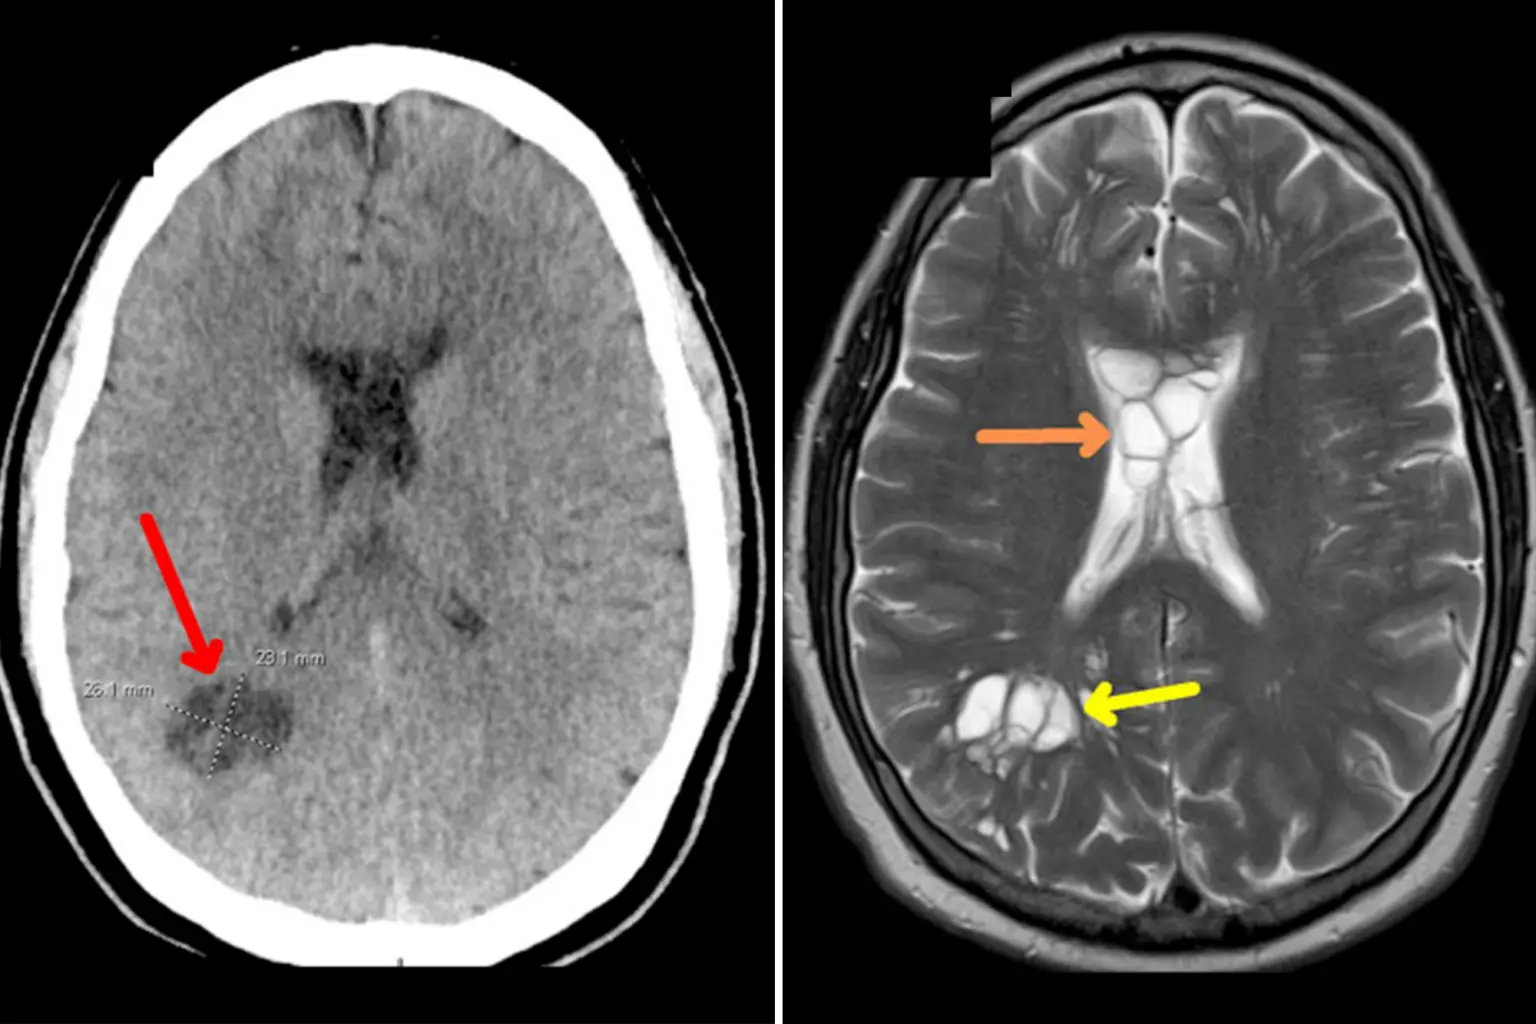

Στην συγκεκριμένη περίπτωση, ο ασθενής εκτός από το οίδημα, ανέπτυξε κύστεις και στις δύο πλευρές του εγκεφάλου του. Αργότερα, αυτό αποδείχθηκε ότι προκλήθηκε από τo παράσιτο (κεστοειδής σκώληκας) που είχε γεννήσει αυγά μέσα στον εγκέφαλο του άνδρα.